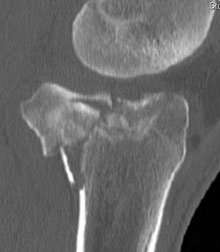

any obvious breaks, and the things we are looking for here include patellar fracture (X-ray on left shows the patella broken in two), tibial plateau fracture (X-ray on the right shows the tibial plateau shattered into bits), osteochondral injury (small flake of bone knocked off) or perhaps even a Hoffa’s fracture which is an eponymous name which is used for a fracture which occurs at the back of the femur where part of the articular surface (joint surface) and bone break free.Plateau fractures and fractures in general are thus picked up by the X-rays but you do need to get a full series of four X-rays – an AP view, a lateral view, a skyline view, a Rosenberg or Schluss view which is the tunnel view and which shows the osteochondral injury. Someone senior needs to look at the X-rays as the signs may be subtle and easily missed.